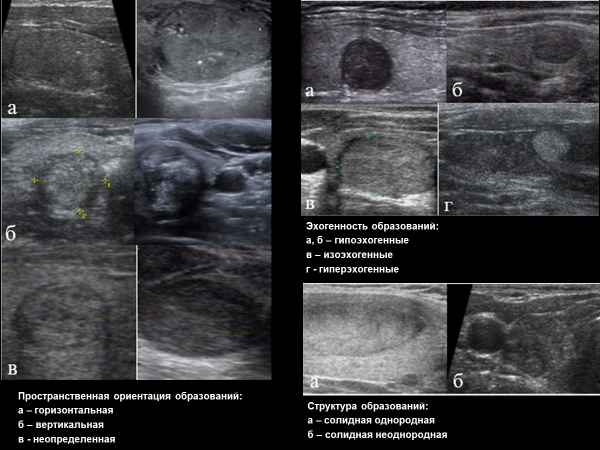

• Пространственная ориентация: горизонтальная (ширина больше высоты); вертикальная (высота больше ширины) - определяется на поперечном срезе; неопределенная или шаровидна/округлая (должна определяться как на поперечном, так и на продольном срезах).

• Эхогенность: снижена значительно (эхогенность ниже ткани ЩЖ и мышц шеи); снижена умеренно (ниже ткани ЩЖ, но не ниже мышц шеи); узел изоэхогенный относительно окружающих тканей ЩЖ; узел гиперэхогенный относительно окружающих тканей ЩЖ.

• Структура: солидная однородная (гомогенная); солидная неоднородная (негомогенная, гетерогенная); солидно-кистозная с преобладанием солидного компонента; кистозно-солидная с преобладанием кистозного компонента; преимущественно кистозная (с пристеночными включениями, взвесью, с пристеночным тканевым компонентом); кистозная. При размере кист до 1 см их можно называть макрофолликулами, при размере более 1 см используется термин «коллоидная киста». Встречается «губчатые (спонгиформные) узлы», которые полностью состоят из множественных мелких кистозных структур.